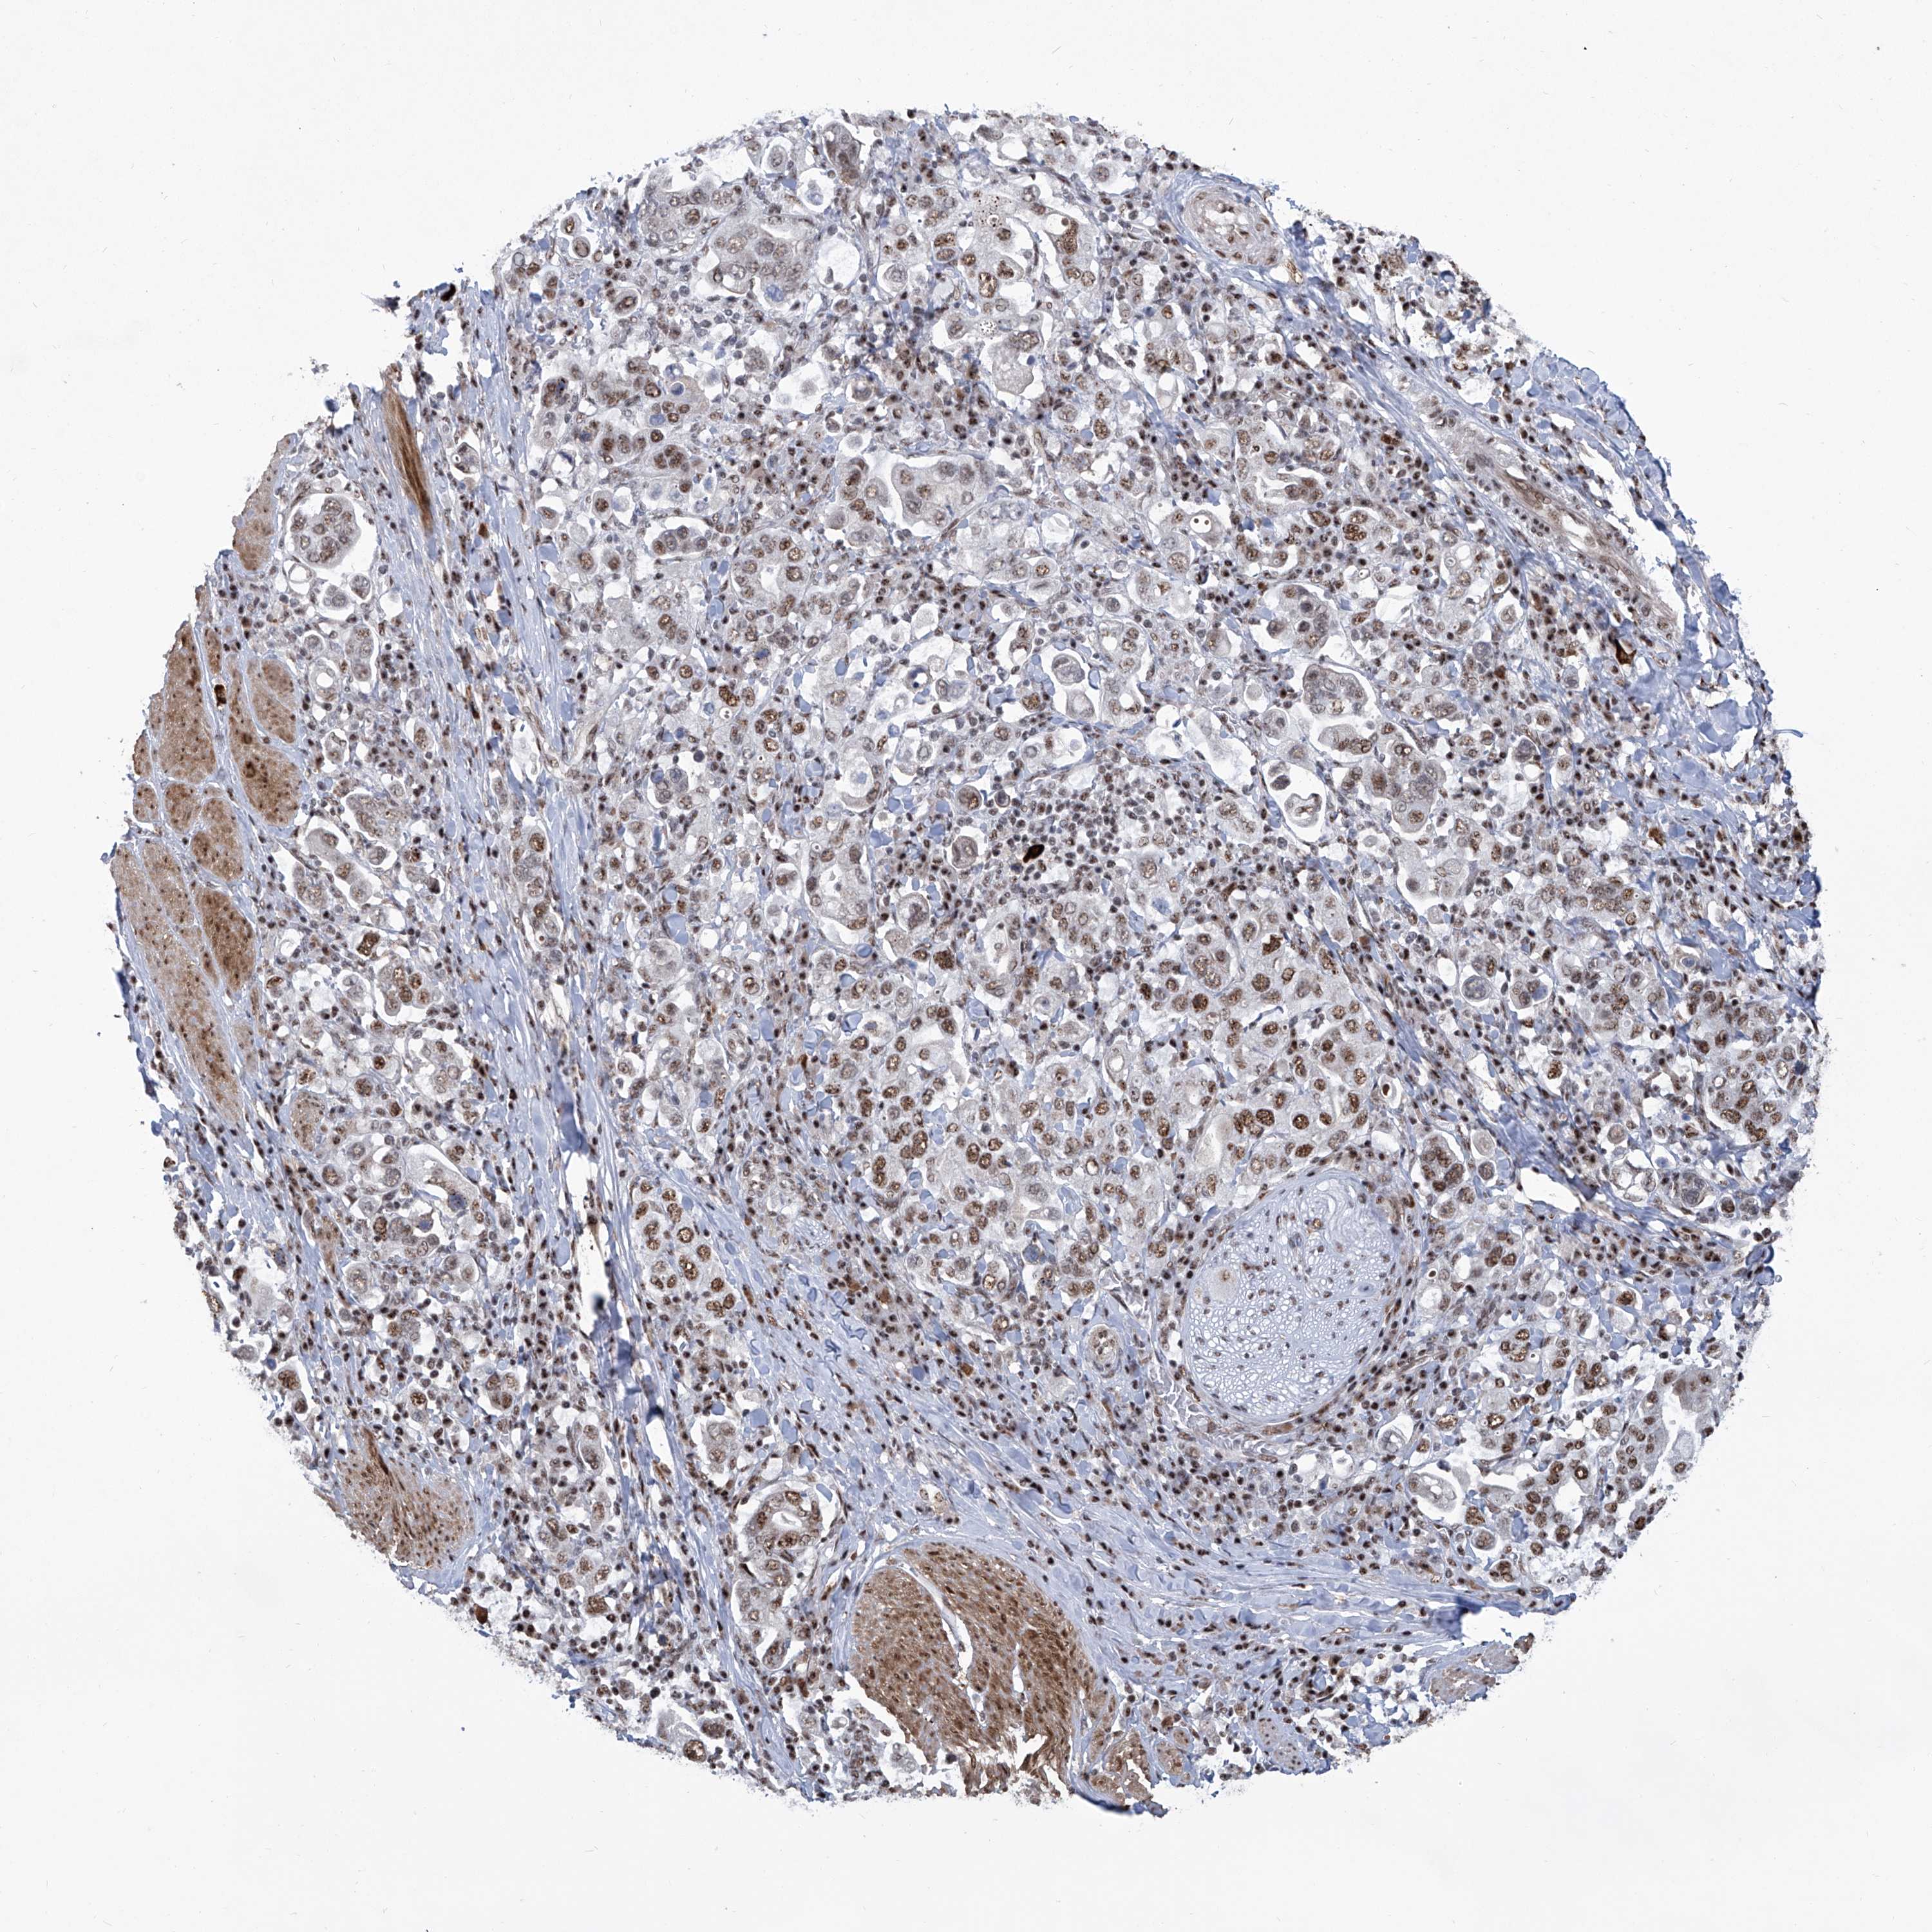

STOMACH CANCER - Protein expressioni

A mouse-over function shows sample information and annotation data. Click on an image to view it in a full screen mode. Samples can be filtered based on level of antibody staining by selecting one or several of the following categories: high, medium, low and not detected. The assay and annotation is described here.

Antibody stainingi

Antibody staining in the annotated cell types in the current human tissue is reported as not detected, low, medium, or high, based on conventional immunohistochemistry profiling in selected tissues. This score is based on the combination of the staining intensity and fraction of stained cells.

Each image is clickable and will lead to virtual microscopy that enables deeper exploration of all samples and also displays staining intensity scores, fraction scores and subcellular localization as well as patient and tissue information for each sample.

Antibody HPA029140

Antibody CAB033362

Staining

High

Medium

Low

Not detected

Intensity

Strong

Moderate

Weak

Negative

Quantity

>75%

75%-25%

<25%

None

Location

Nuclear

Cytoplasmic/membranous

Cytoplasmic/membranous,nuclear

Adenocarcinoma, NOS

Adenocarcinoma, High grade